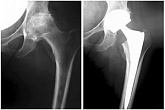

Hüftendoprothetik

In den späten Stadien der Arthrose des Hüftgelenks, mediale Frakturen des Schenkelhalses in der älteren Altersgruppe, ist die einzige Möglichkeit, sich zu erholen, das betroffene Gelenk durch eine künstliche Gelenkarthroplastik zu ersetzen.

Diese Methode ermöglicht es Ihnen, die Gliedmaße, das volle Volumen der Bewegungen im betroffenen Gelenk, zurückzugeben, um von ständigem Schmerz und Knirschen während der Bewegungen zu sparen und folglich den Patienten zu einem vollen aktiven Leben zurückzubringen.

Im Folgenden werden Röntgenaufnahmen und Fotografien vorgestellt, die das Ausmaß der Bewegung im betroffenen Gelenk vor und nach der Operation zeigen.